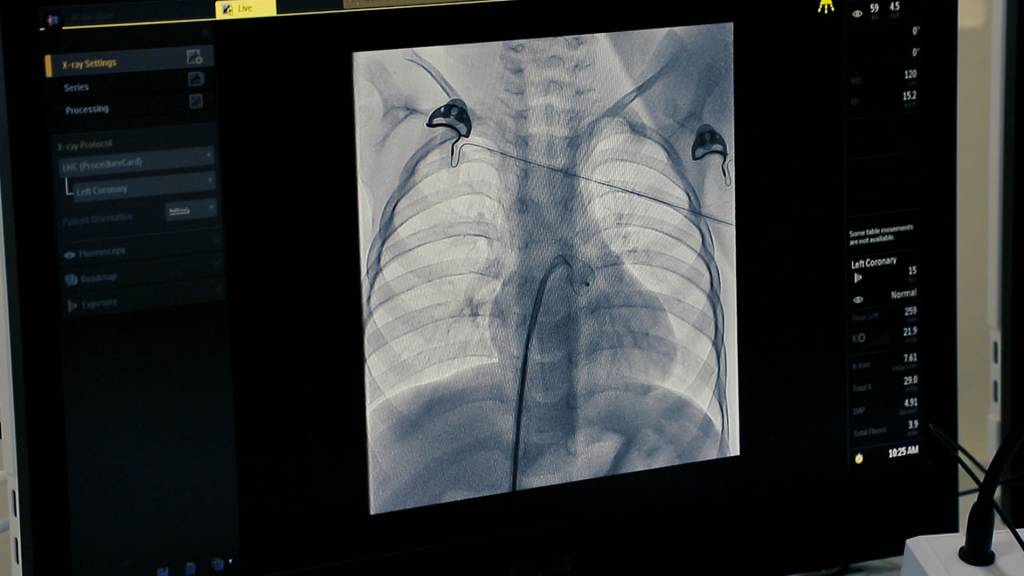

Kuni kecha 4 nafar yuragida tug‘ma nuqsoni bor bolalarda murakkab jarrohlik amaliyotlari o‘tkazildi. 3 nafarida yopiq, 1 nafarida esa ochiq usulda yurakdagi tug‘ma nuqson to‘liq bartaraf etildi. Bu xayrli ish Bolalar milliy tibbiyot markazining yuqori malakali shifokorlari bilan hamda viloyat Sog‘liqni saqlash boshqarmasi tasarrufidagi muassasalari xodimlari hamkorligida qilindi.

Tumandagi Gulzor mahallasida yashovchi Navbahor Qudratovaning kenja o‘g‘li hozir ikki yoshda. Afsuski u uch oyligida o‘tkazilgan tibbiy tekshiruvlarda yuragida teshigi borligi aniqlangan edi. Shundan buyon bolada muttasil ahvoli yomonlashavergan. Oila kattalari bolani bu ahvoli og‘irlashganini bilib tuman avval viloyat shifokorlariga keyin poytaxtga davolagani olib borgan. Aksiya doirasida bu ayolning o‘g‘li yuragida ham yopiq tibbiy amaliyot o‘tkazildi. Tez fursatda jarayonlar ijobiy tarzda yakunlandi.